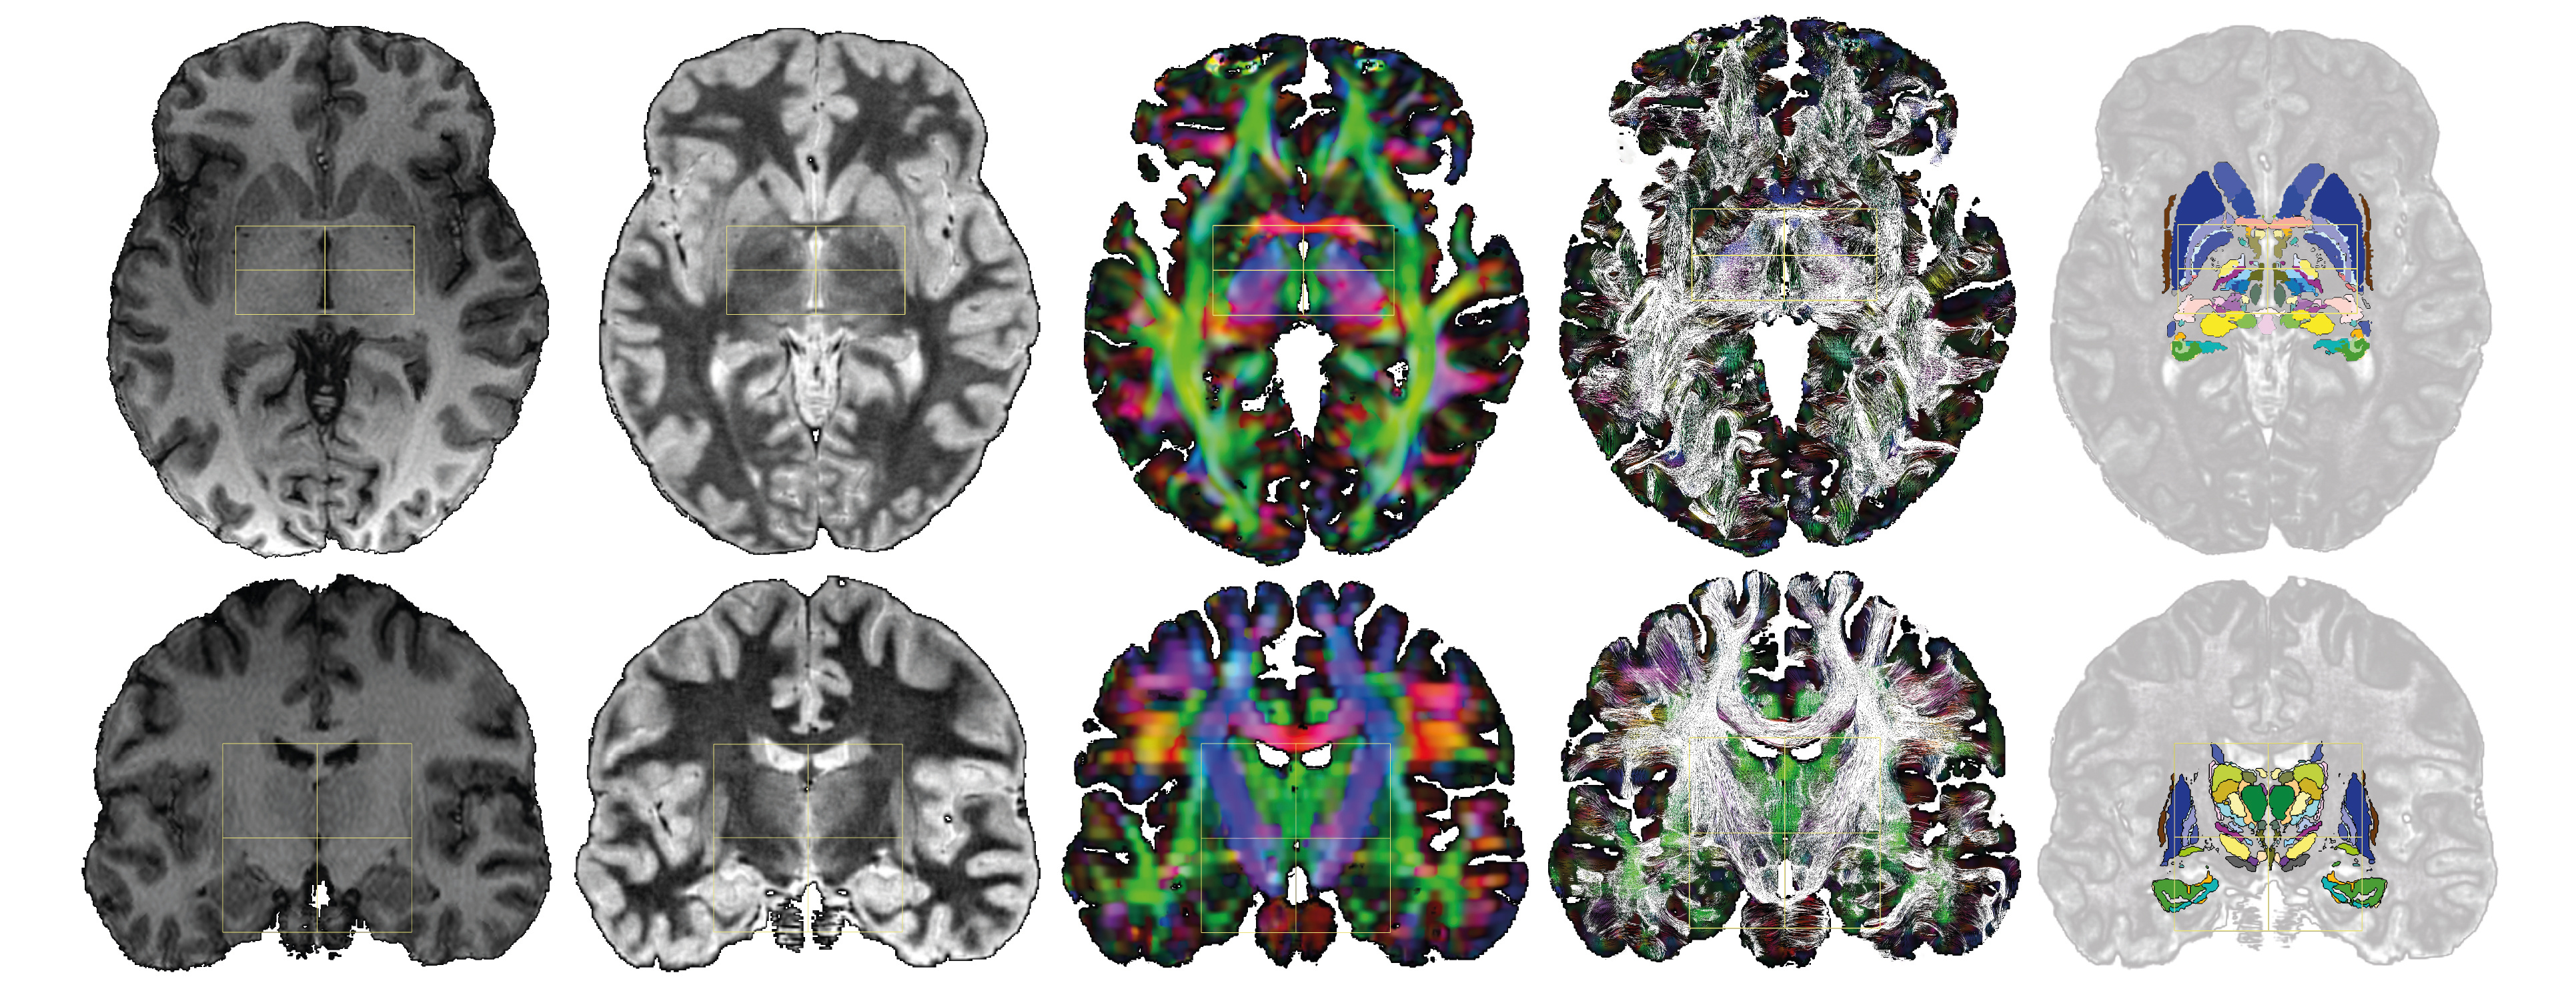

The normalized image datasets (T1, WAIR, and DEC) displayed advanced architectural information, with WAIR images providing much more detail than T1. The DB-MA atlas is designed to be fully compatible with ICBM152 and CIT168 population-based atlases, allowing for flexible atlas combinations and orientations.

Figure 2: DB-MA atlas datasets: left to right, T1, WAIR, DEC, DTI-FT and eMDBA (coloured surfaces); axial horizontal plane through ACPC (top row); coronal plane through the midpoint between AC and PC (bottom row); ACPC system (yellow box), x-width 60 mm, y-length (ACPC length) 30 mm, z-height 60 mm.